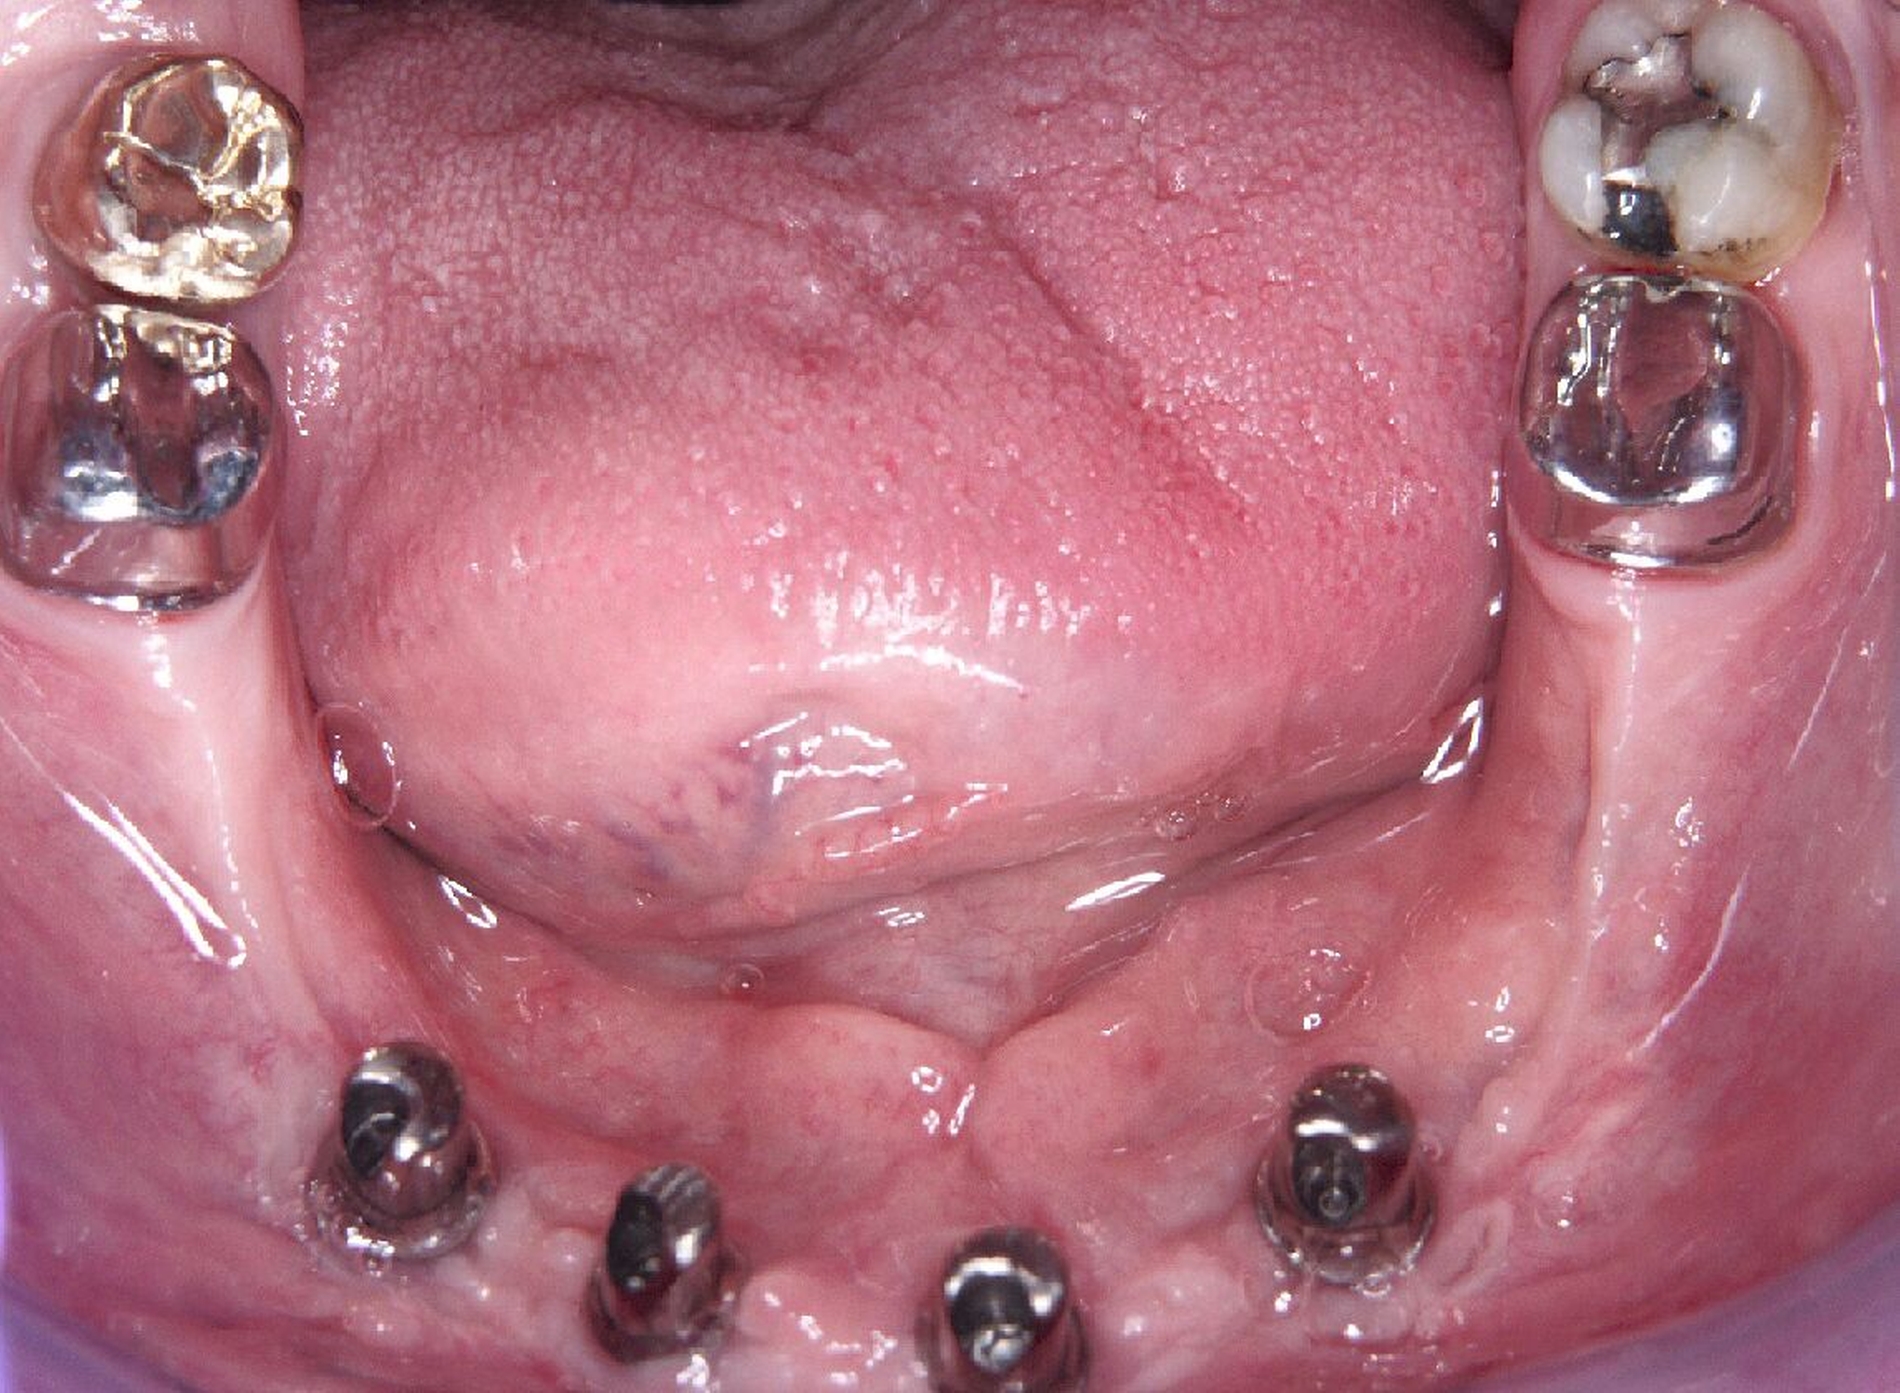

Nachdem der Patient bei einem Berufsunfall mit Ausnahme der zweiten Molaren und der Weisheitszähne alle Zähne im Unterkiefer verloren hatte, erfolgte 1996 im Alter von 44 Jahren die definitive Lückenversorgung. Hierzu wurden eine verschraubte Brückenkonstruktion (044-034-043-044) sowie zwei verblockte Kronenpaare auf insgesamt acht Implantaten eingesetzt. Nach sieben Jahren Tragedauer wurde an mehreren Implantaten röntgenologisch ein Knochenabbau festgestellt. Verkürzte Kontrollintervalle mit professionellen Zahnreinigungen und intensiven Instruktionen zur Interdentalhygiene konnten nicht verhindern, dass nach weiteren sieben Jahren Anfang 2011 der Knochenverlust an den meisten Implantaten auf 50 bis 80 Prozent zunahm (Abb. 1a).

Die Entscheidung zur Explantation fiel wegen des beschleunigten Knochenverlusts und der extrem erschwerten Bedingungen für eine effektive Mundhygiene im Bereich der Implantate mit Sondierungstiefen bis zu 12 mm (Abb. 1b und 1c). Unter Lokalanästhesie wurden sieben der acht Implantate mit einem passenden Trepanbohrer mit 0,1 mm Aufmaß im Vergleich zum Außendurchmesser der Implantate umbohrt, anschließend mit einem kleinen Rasparatorium gelockert und dann mit einer Arterienklemme entfernt. Entscheidend für die Eignung der Trepanbohrer war die Längenmarkierung, um eine Nervverletzung bei der Entfernung der sehr tief gesetzten Seitenzahnimplantate zu vermeiden (Abb. 1d und 1e). Eine ausgedehnte Lappenbildung konnte durch dieses Vorgehen vermieden werden.

Eine präoperativ vorbereitete Interimsprothese, die über zwei gegossene Bonwill-Klammern sowie das verbliebene Implantat in regio 35 stabil abgestützt war, diente gleichzeitig als Verbandsplatte (Abb. 1f). Auf eine Glättung scharfer Knochenkanten oder die Nivellierung der Kieferkämme wurde verzichtet, um einen iatrogenen Knochenverlust zu vermeiden und das regenerative Potenzial des verbliebenen Knochens zu nutzen (Abb. 1g). Bereits bei der röntgenologischen Kontrolle nach drei Monaten war eine deutliche Zunahme des Knochens im Bereich der alten Implantatpositionen zu erkennen (Abb. 1h). Eine Nachimplantation von vier Implantaten in den Positionen 32, 34, 42 und 44 erfolgte neun Monate nach der Explantation und einer vorangegangenen Verbesserung der Weichgewebsbedeckung durch multiple freie Schleimhautransplantate vom harten Gaumen. Die knöcherne Regeneration unter der gut abgestützten Modellgussprothese verlief so günstig, dass sich der vertikale Höhenverlust des Alveolarkamms im Bereich der gescheiterten Implantate auf circa 2 mm begrenzen ließ. Das zur Entlastung der Kieferkämme und der einheilenden Implantate außerordentlich hilfreiche Implantat in regio 35 wurde erst nach dem Einheilen der nachgesetzten Implantate entfernt. Nach der Einheilzeit der Implantate von weiteren drei Monaten wurde eine kombiniert Zahn/Implantat-gestützte Teleskopprothese mit intraoral verklebten Galvano-Sekundärkronen eingegliedert (Abb. 1k bis 1m). Inzwischen ist diese, wie eine herausnehmbare Brücke abgestützte UK-Prothese seit zehn Jahren funktionstüchtig ohne Zeichen einer Periimplantitis an den vier Implantaten.